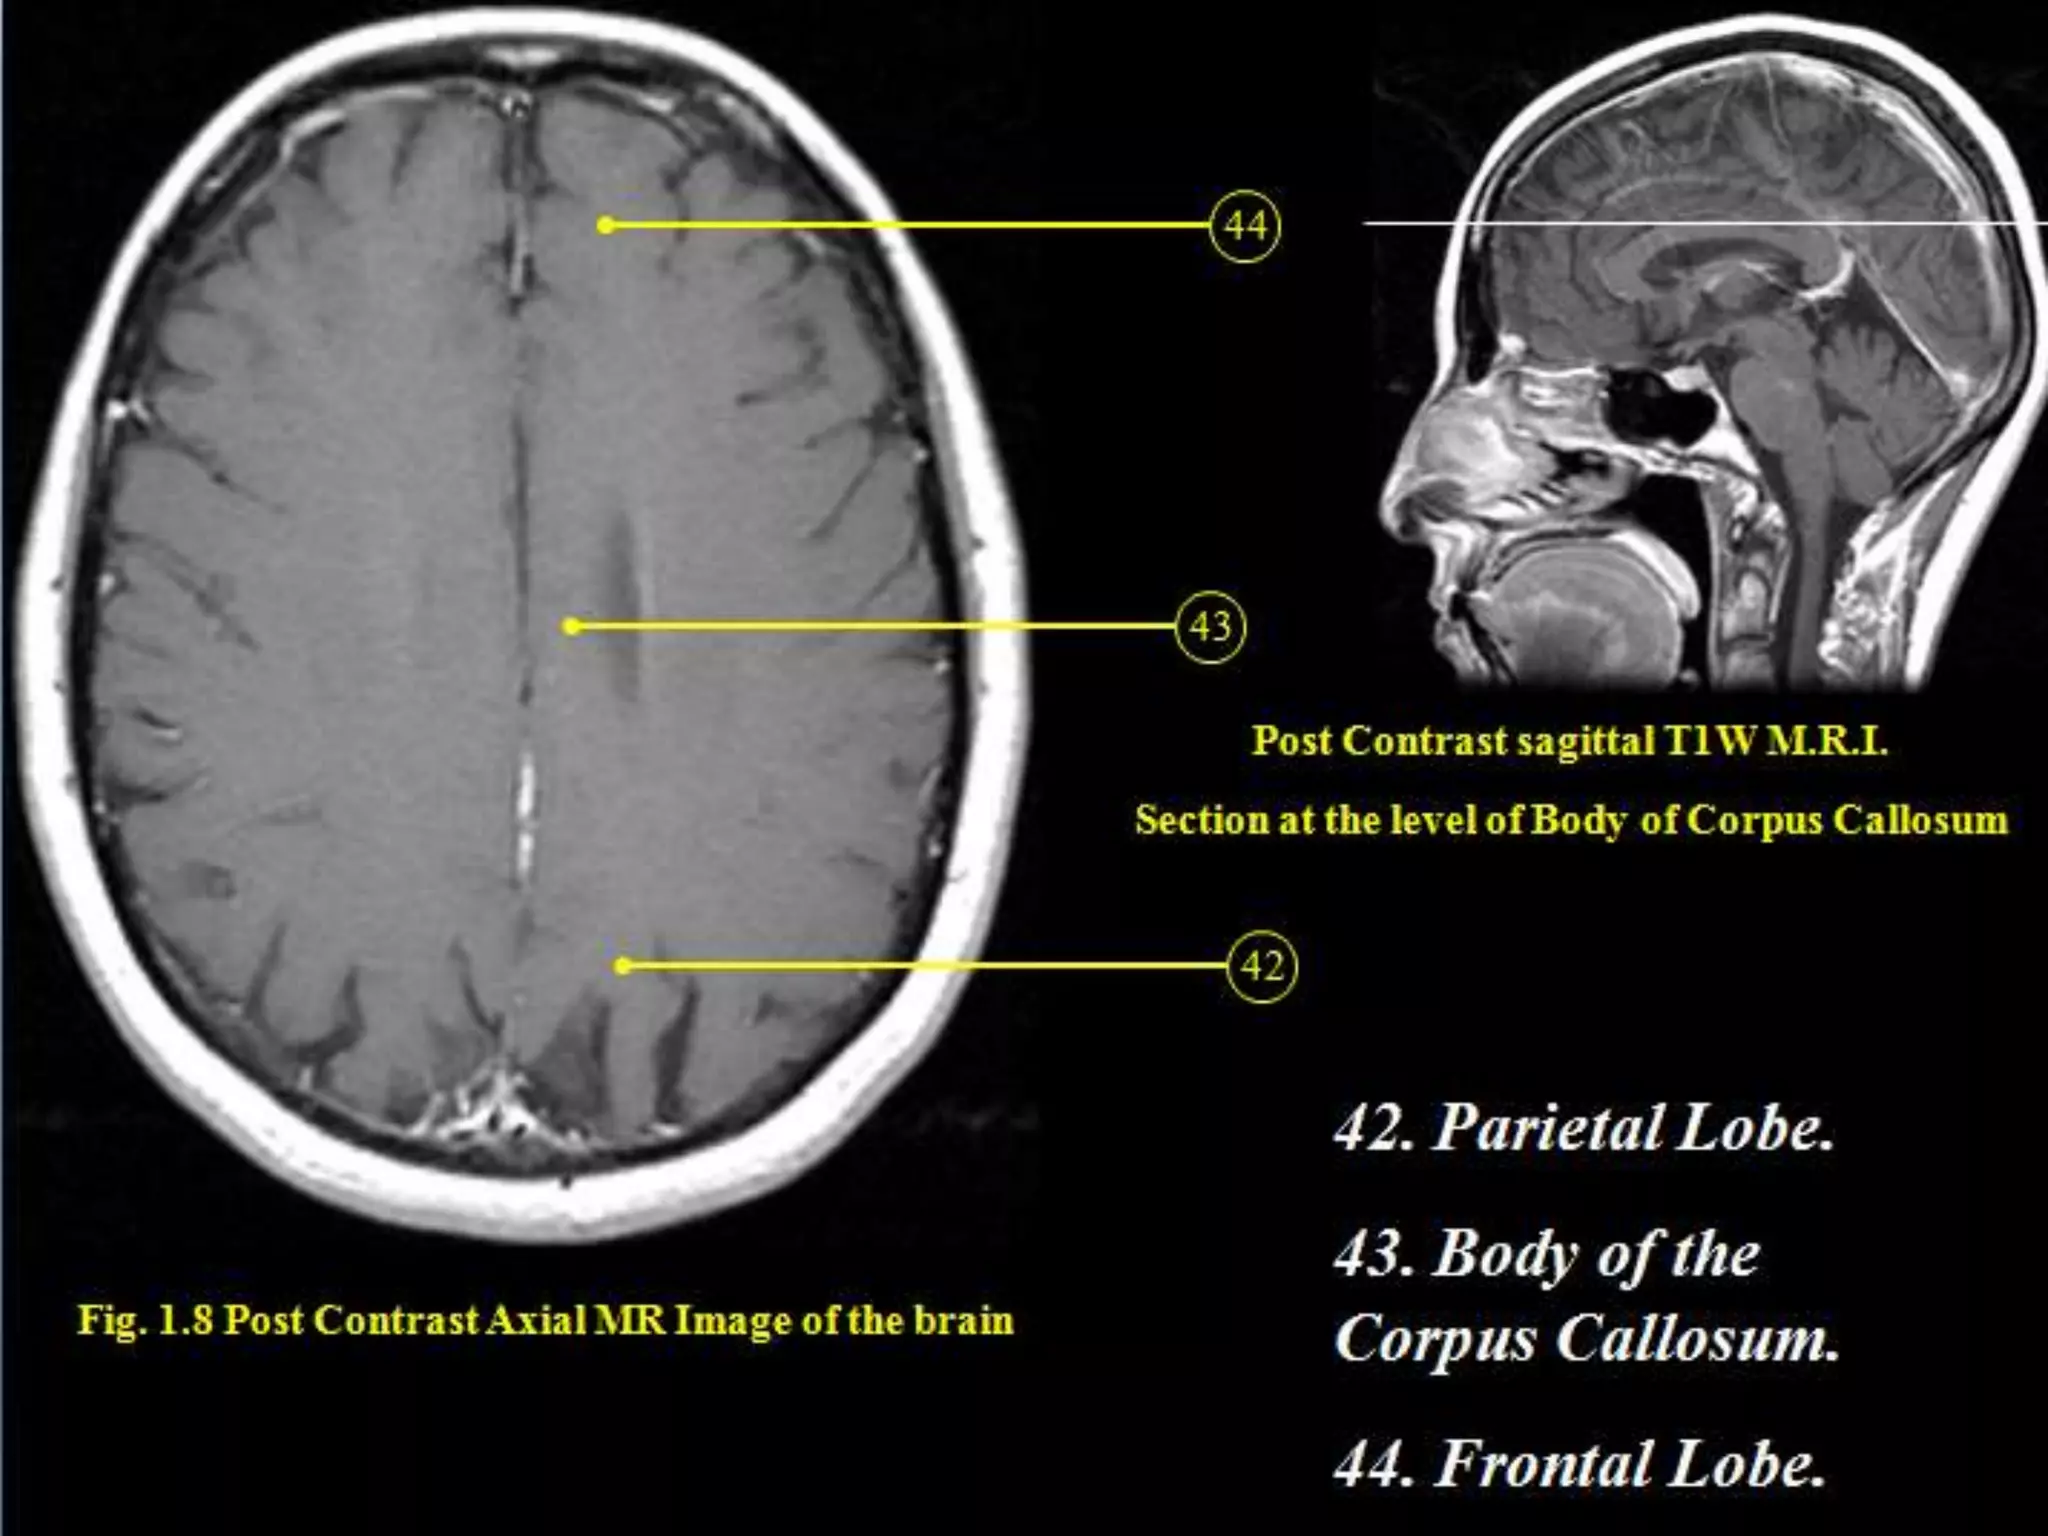

Sectional Anatomy: NormalAxial CT and MRI Anatomy. On CT and MR scans, the brain has been briefly viewed in infratentorial and supratentorial sections, as described below. CT scans are performed with a 15- to 20-degree angulation to the canthomeatal line at 8-mm increments. MRI scans are generally obtained parallel to the AC-PC line in the axial plane with 6-mm slice thickness. Using the sagittal view, the coronal sections are acquired parallel to the brain stem, and the sagittal sections are obtained perpendicular to the axial section. On MRI studies, cranial nerves IX and X can be demonstrated at this level because they emerge from the postolivary sulcus. The posterior aspect of the cerebellar hemispheres is outlined by the inferior portion of the cisterna magna.